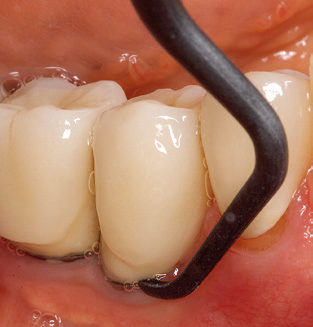

Good illumination of the working field facilitates the process considerably. The system used by the authors achieves this thanks to a 5x LED ring integrated in the handpiece. Naturally, a range of working tips for different indications is also offered. A straight, universally employable tip is the basic instrument required for machine cleaning of natural teeth (Fig. 5a and b). Curved tips, which allow access to exposed furcations, are also available for hard-to-reach areas in the posterior region (Fig. 6).

Of course, working tips for the cleaning of implant surfaces are also indispensable for SPT in patients fitted with implants. The implant cleaning attachment on the system used here is characterised by its tapered, hexagonal design. This design allows light, atraumatic penetration of the peri-implant pocket and displays a good cleaning performance (Fig. 7).